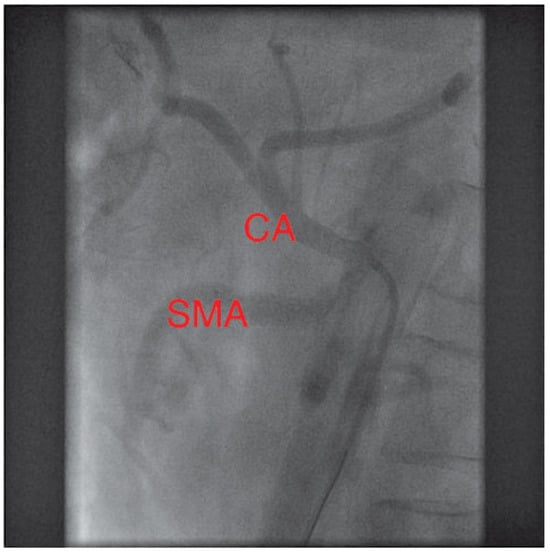

In a first step, the SMA was treated by balloon angioplasty and a bare metal stent (hippocampus 7.0/20 mm) was implanted. After 2 weeks, the patient was readmitted with improved but not completely resolved abdominal symptoms. The remaining stenosis of the CA was revascularised, using another bare metal stent (hippocampus 6.0/20 mm). During a clinical follow-up of six months, the patient was asymptomatic.

Figure 4. Final result: both splanchnic arteries (SMA and CA) are now open.

Uncertainty exists, regarding whether two or more vessels need to be severely stenosed for patients to be symptomatic. Our patient became asymptomatic only after sequential treatment of both stenosed mesenteric arteries, questioning the classic doctrine.